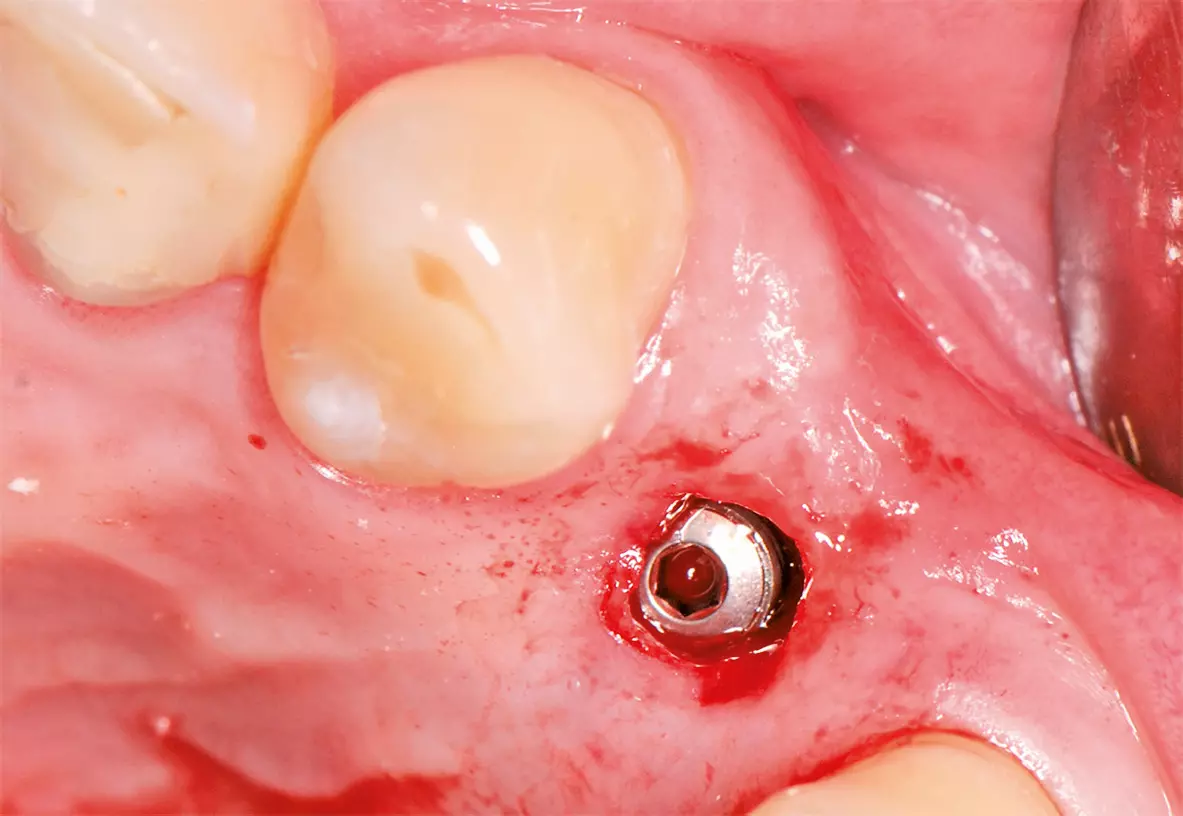

Nach ausführlicher Aufklärung und Beratung wurde die Extraktion des Zahnes 24 geplant. Zu diesem Zeitpunkt entschied sich der Patient gegen eine präventive Maßnahme zur Versorgung der Extraktionsalveole. Eine schonende Extraktion des Zahnes erfolgte komplikationslos unter gängiger Lokalanästhesie. Dabei konnte die vestibuläre Lamelle regelrecht erhalten werden (Abb. 2). Die Extraktionsalveole wurde mit einer Naht versorgt (Abb. 3). Ein Tag nach der Extraktion zeigt sich eine fibrinbelegte Wunde mit zeitgerechter und regelrechter Wundheilungsstatus (Abb. 4). Nach einer Woche wurde die Naht entfernt. Es zeigte sich zu diesem Zeitpunkt weiterhin eine fibrinbelegte Wunde mit einer okklusalen Mulde, die etwa 5 mm tief ist. Die Heilung war nach einer Woche also noch nicht komplett abgeschlossen (Abb. 5). In der frühen Wundheilungsphase berichtete der Patient beschwerdefrei gewesen zu sein. Drei Monate später stellte sich der Patient erneut vor mit dem Wunsch einen festsitzenden Zahnersatz zu bekommen. Die Extraktionsalveole zeigte eine vollständige Wundheilung und eine deutliche vestibuläre Knochenresorption (Abb. 6). Das Implantat konnte trotzdem eingesetzt werden und zeigt zum Zeitpunkt der Implantation eine adäquate Primärstabilität (Abb. 7). Nach drei Monaten wurde das Implantat freigelegt (Abb. 8) und anschließend mit einer Krone versorgt (Abb. 9).

Ein Implantat konnte erfolgreich in regio 24 mit einer ausreichenden Primärstabilität inseriert werden (Abb. 20). Nach drei Monaten wurde das Implantat freigelegt (Abb. 21) und anschließend mit einer Krone versorgt (Abb. 22).